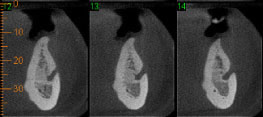

Paciente com história clínica de trauma. Fratura no côndilo direito com deslocamento do fragmento para medial e deslogamento do côndilo para lateral da cavidade articular.